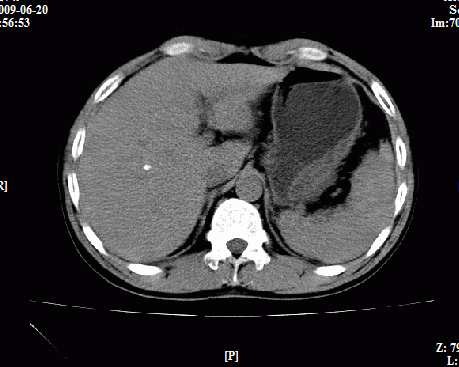

以下是引用随光逐影在2009-6-23 11:37:00的发言:[br]1)考虑胃癌;建议行胃镜检查进一步明确诊断。2)肝右叶肝内胆管结石(或钙化)。

以下是引用zxl51642在2009-6-23 11:31:00的发言:[br]胃大弯侧壁明显增厚呈软组织肿块,考虑胃癌可能性大,建议胃镜活检。